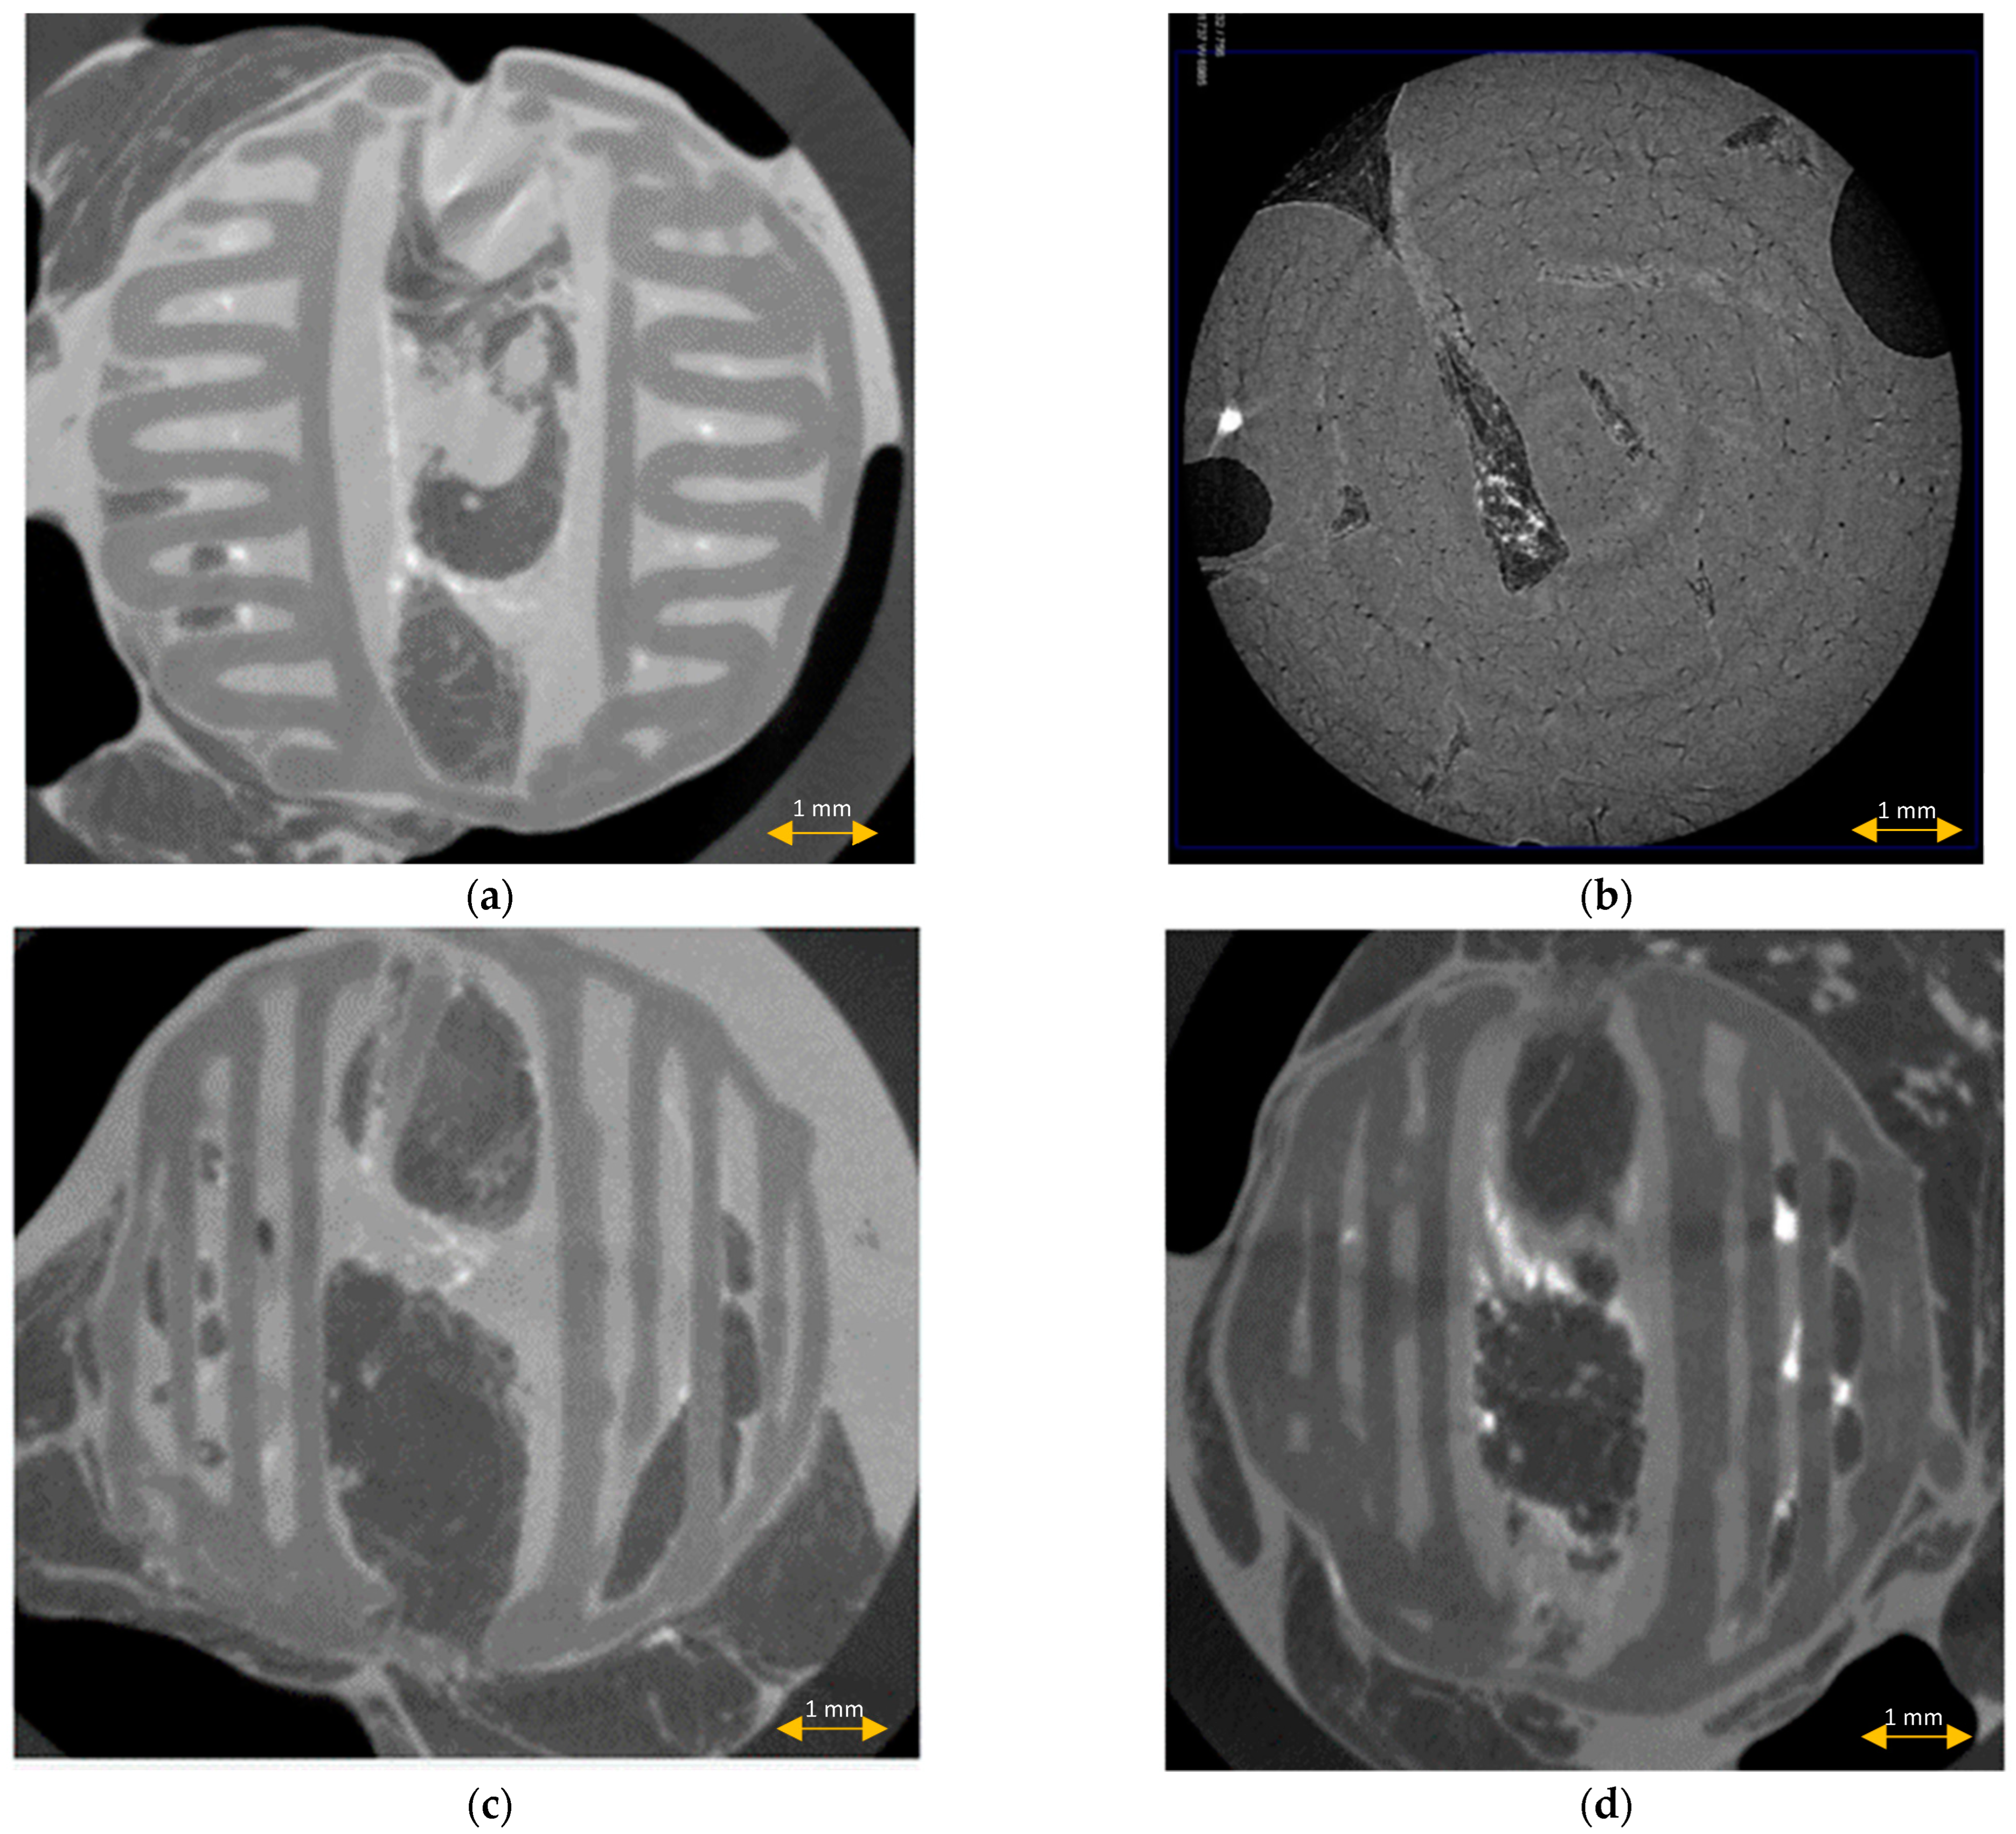

3.1. Scaffold Characterization

3.5. Scaffold μCT Imaging